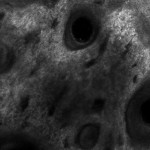

Il miscroscopio confocale consente quindi di visualizzare le strutture cellulari della pelle in sezioni orizzontali con uno spessore inferiore ai 5 µm, rendendo per la prima volta possibile una biopsia ottica in tempo reale.

La procedura è molto semplice e totalmente indolore: il medico appoggia la sonda del microscopio sulla lesione da analizzare, dopodiché una luce laser a bassa potenza viene convogliata sulla pelle in maniera che penetri nel punto richiesto; la luce riflessa e non assorbita dalle strutture cutanee viene rilevata dal microscopio e questo permette di osservare una sezione orizzontale degli strati cellulari cutanei ad una specifica profondità. Il microscopio confocale permette la scansione e l’analisi degli strati cutanei a differenti profondità, osservando dunque le caratteristiche delle cellule e valutandone la possibile malignità.